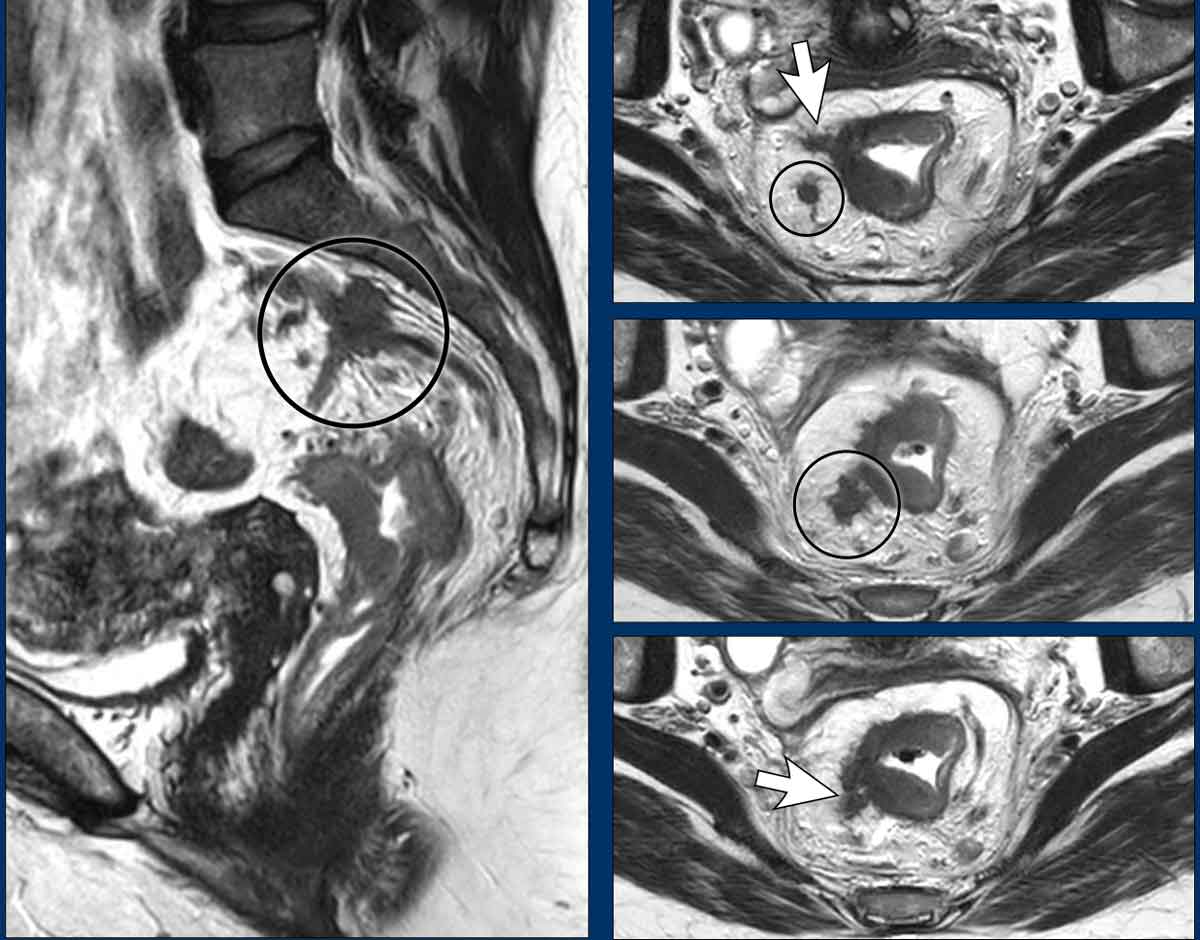

Rectal adenocarcinomas usually originate from adenomas, which may be:

• Polypoid: Raised on a stalk or focal attachment, often low-grade (T1–T2), projecting into the lumen.

• Sessile: Flat, broad-based, typically presenting as partial or complete annular wall thickening.

Invasive Margin: The tumor’s attachment site to the rectal wall—the invasive margin—is the site where the tumor may invade beyond the rectal wall, and is therefore critical for T-staging and assessing extramural extension.

Tumor Circumference: Describe the degree of wall attachment in the report using either:

• Clock-face notation (e.g., “from 3 to 7 o’clock”)

• Prose (e.g., “left anterolateral”).

• Typically presents as long-segment, diffuse bowel wall thickening

• Submucosal growth pattern, yielding a "target" appearance on axial images

• Diffuse mesorectal fat infiltration is common

Images

The provided images demonstrate a signet-ring cell carcinoma with diffuse rectal wall thickening, the classic target appearance, and mesorectal fat infiltration.